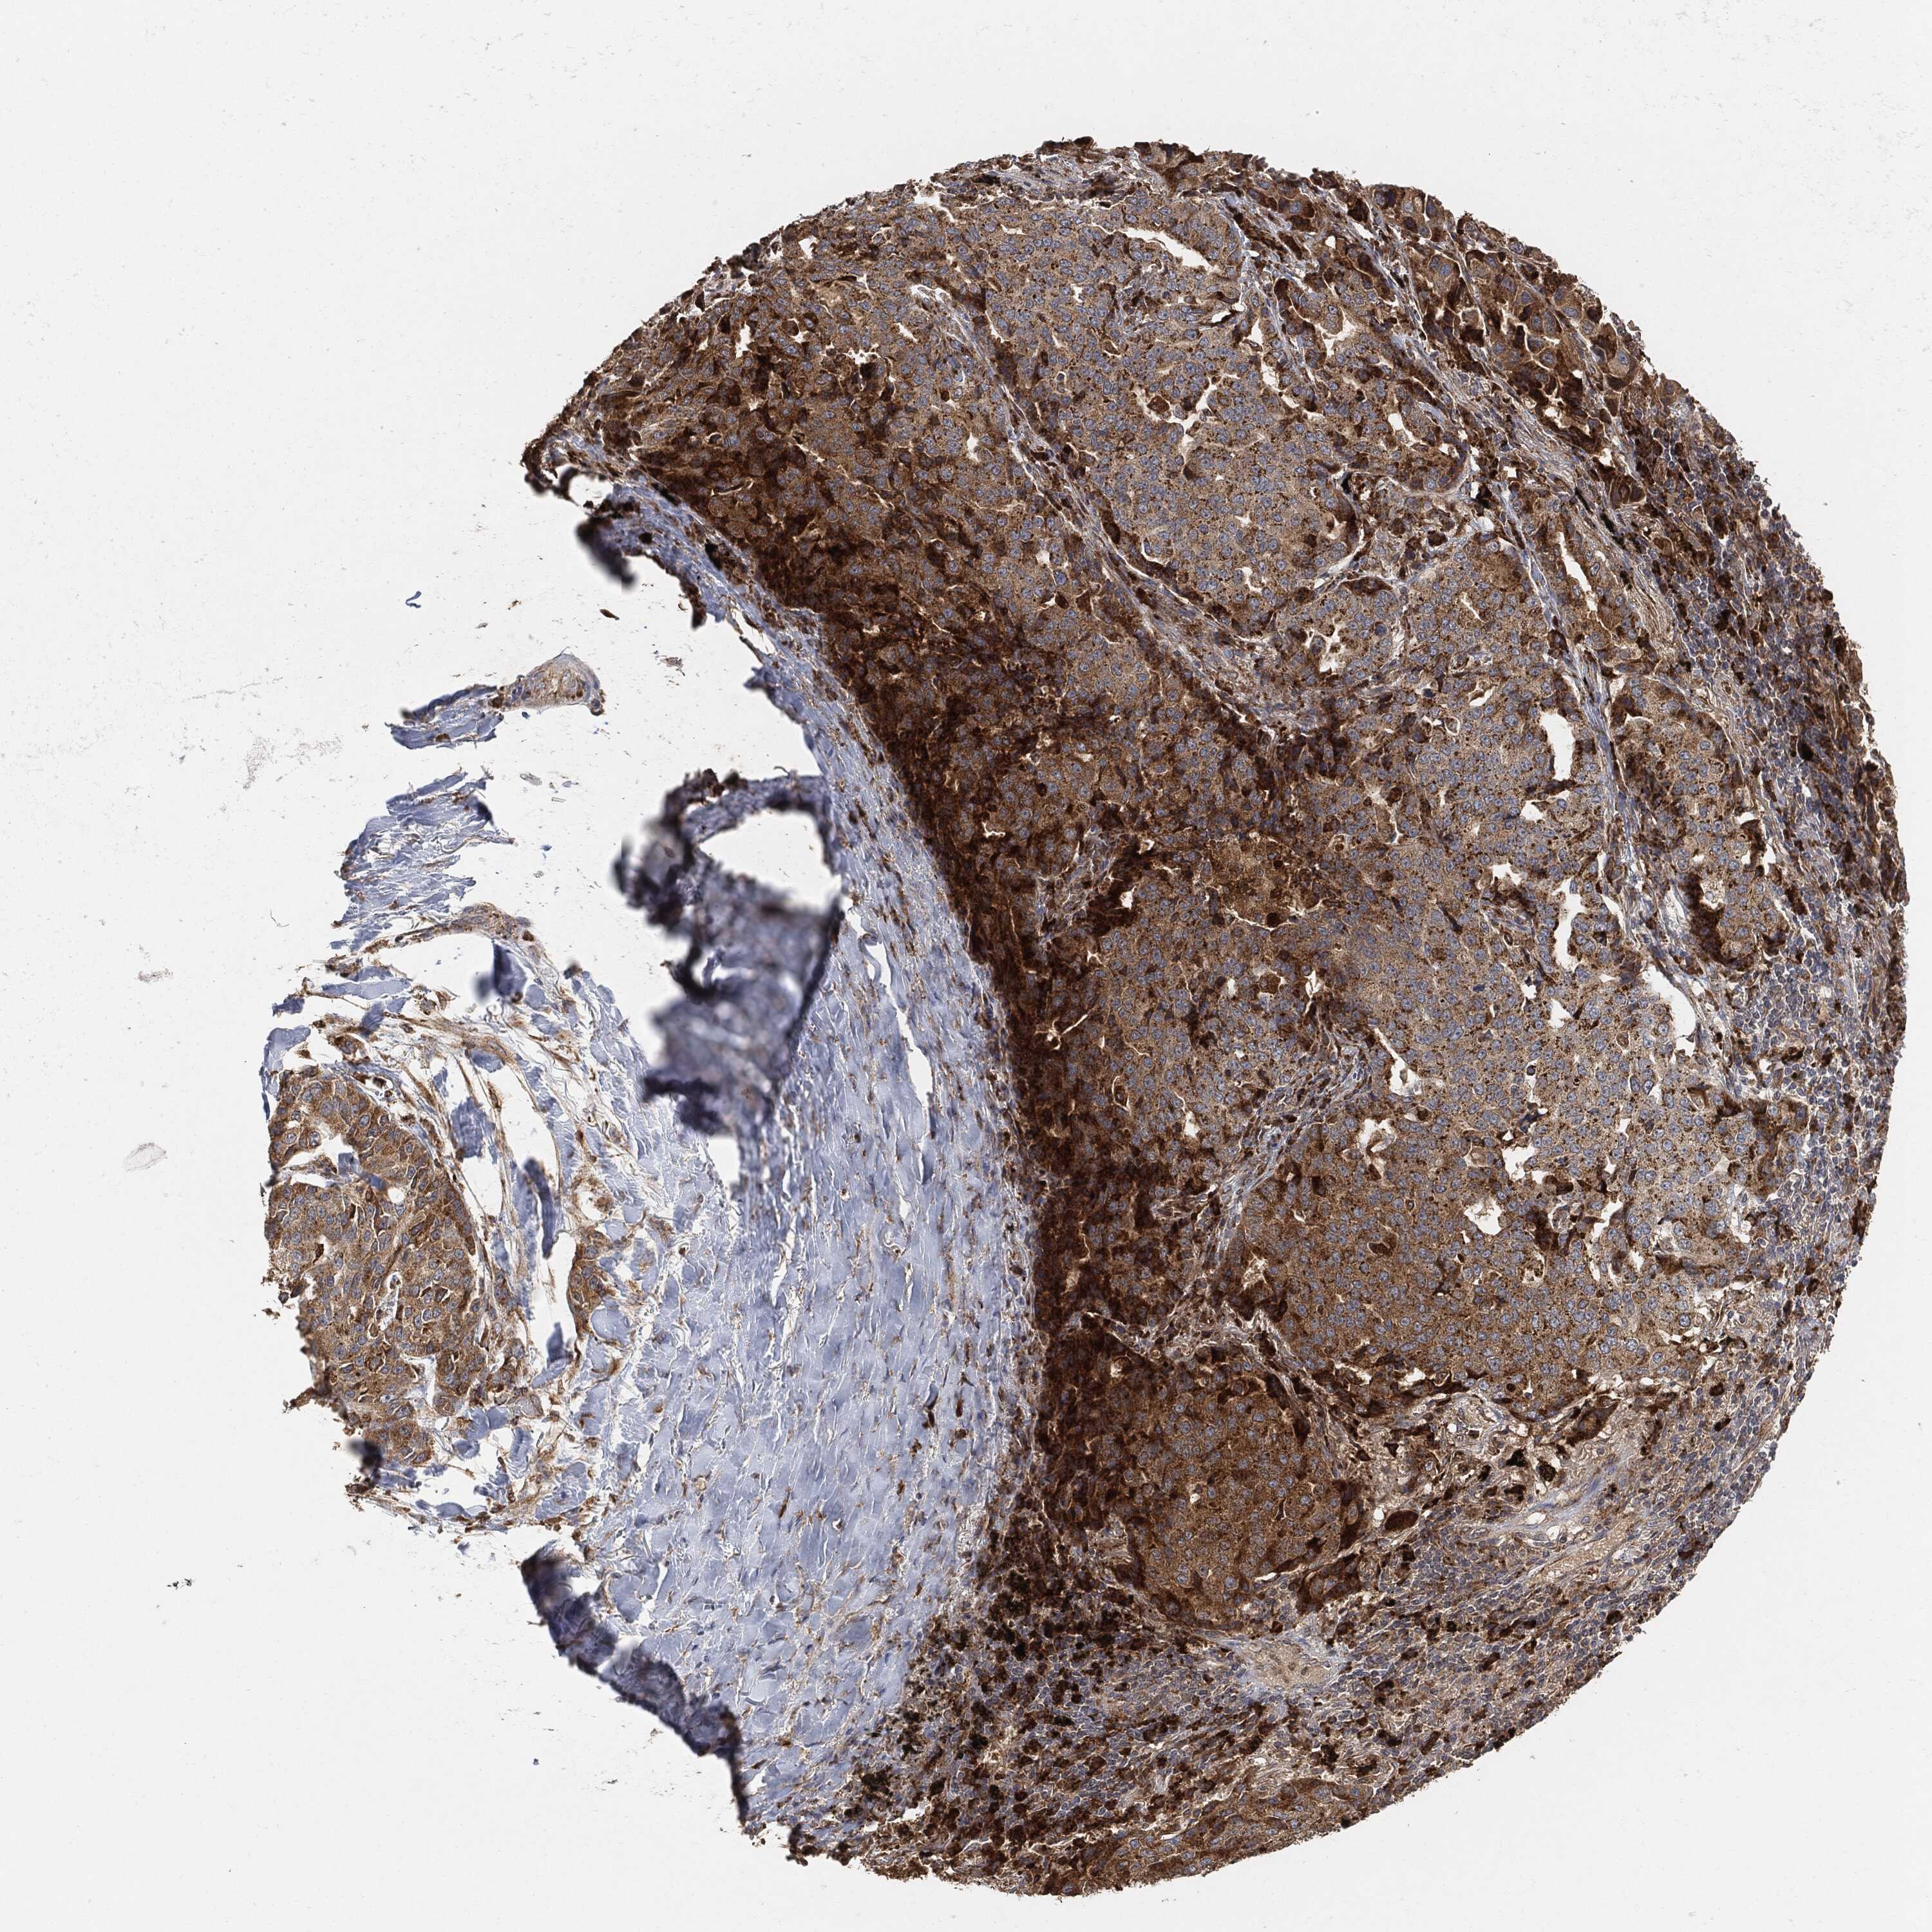

CANCER LUNG CANCER Show tissue menu